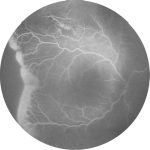

Fig. 6 Foto fundus, OCT strutturale e OCT-angiografia di un bambino di 7 anni affetto da anisometropia, fibre mieliniche del NO e strabismo divergente.